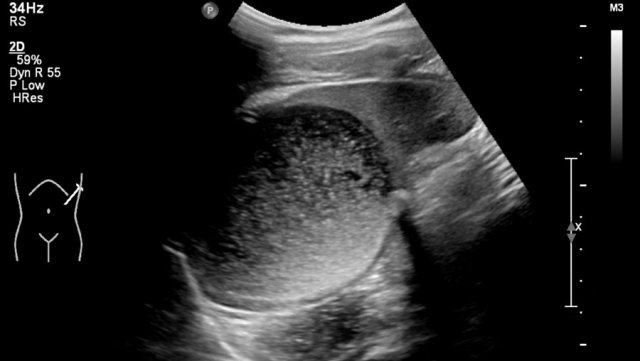

One-year-old boy was referred with a diagnosis of a cystic nephroblastoma.

Ultrasound detected a huge cyst in the middle of the abdomen.

When examined from the left flank with a high frequency linear array probe some parenchymal tissue was visible surrounding very dilated calyces. This is compatible with an extreme hydronephrosis.

At first it was thought that there were some solid parts in the cyst.

But when pressure was applied with the probe this proved to be debris.

MRI depicts the hydronephrosis with more overview.

The cause was a pyeloureteric stenosis.

The left kidney had 33% split renal function on renography.

A pyelum reconstruction was successfully performed.